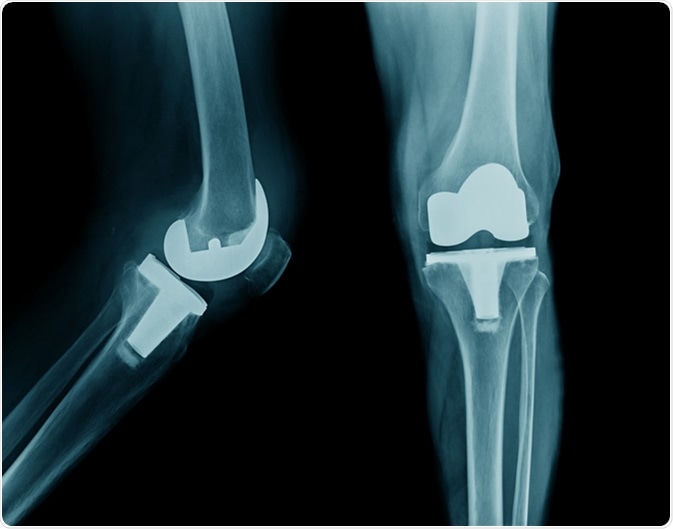

Contrary to popular belief knee replacement consists of resurfacing of the damaged bone with suitable metallic component. The whole bone is not replaced. In fact we try to preserve as much bone as possible.

Our knee joint is made up of three bones : Femur, Tibia and the Patella. In TKR the damaged surface of femur and tibia is replaced. The patella may or may not be replaced depending on the surgeon's judgment.

Modern knee prosthesis are designed to last over 20 years. These are made of extremely durable titanium and cobalt-chrome alloys. The implants are made to behave like the natural knees. With newer implants knee bending up to 130° is possible.